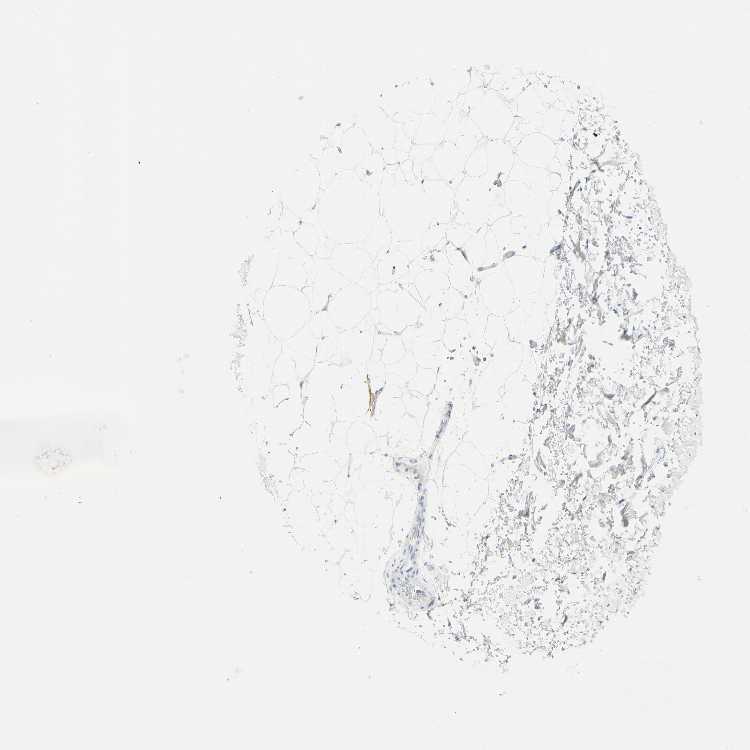

SOFT TISSUE 2 - Antibody stainingi

Antibody staining in the annotated cell types in the current human tissue is reported as not detected, low, medium, or high, based on conventional immunohistochemistry profiling in selected tissues. This score is based on the combination of the staining intensity and fraction of stained cells.

Each image is clickable and will lead to virtual microscopy that enables deeper exploration of all samples and also displays staining intensity scores, fraction scores and subcellular localization as well as patient and tissue information for each sample.

Antibody HPA006154Antibody HPA012012Antibody CAB009454

Fibroblasts Not detectedNot detectedNot detected

Peripheral nerve -Not detected-